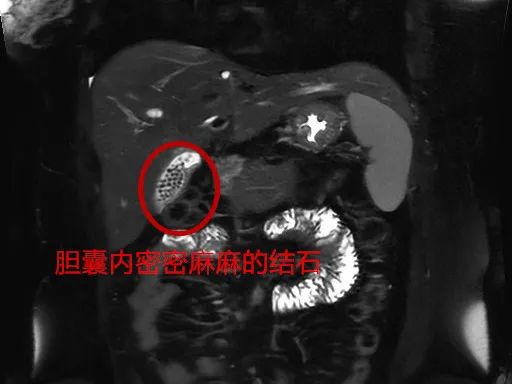

医生了解到,刘女士已婚已育,体形偏胖,平时喜欢喝奶茶、吃油腻的食物,检查发现刘女士的胆囊内竟然充满着大量结石。

手术过程中,外科团队将切除的胆囊打开一看,只见里面密密麻麻,满是形状不一、大小不规则的结石,足足有近百颗。